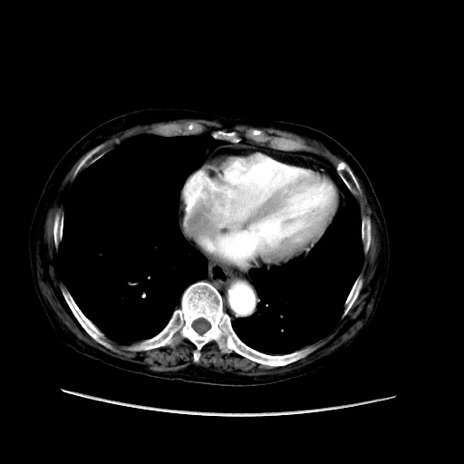

症例31(横断像)

【症例】80歳代 女性

【主訴】腹部膨満感

【現病歴】他院にて肝硬変にてフォロー中。1週間前から便秘、腹部膨満感、臍部腫瘤あり受診となる。

【既往歴】肝硬変

【身体所見】腹部膨隆あり、皮膚変化なし、疼痛なし。

【データ】WBC 4600、CRP 0.25